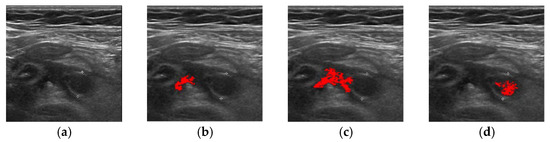

| Method | Successful Images/Total Images |

|---|---|

| FCM | 83/100 |

| ORFCM | 88/100 |

| DFCM | 91/100 |

| DORFCM | 98/100 |

| Accuracy | Precision | Recall | |

|---|---|---|---|

| DORFCM | 84.20% | 83.40% | 85.80% |

| DFCM | 80.80% | 80.90% | 80.20% |

| DORFCM | 84.82% | 83.78% | 86.04% |

| ORFCM | 81.23% | 78.56% | 80.53% |